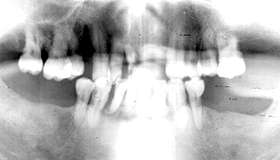

初診時 パノラマ 10年後 パノラマ

73歳 男性 上顎臼歯部の歯は全て脱離または二次カリエスにより崩壊

残存歯は、上顎:76543 45、下顎:84321 137、の計15本。カリエスや根尖病巣が随所に 見られ決して良好な状態とはいえない状況であった。

学校の校長先生を勤められていたとのことで、全身の健康状態は良好で性格も生真面目な感じで 治療やメインテナンスに対する理解も深かそうであった。 インプラントを植立する骨植も良好で、年齢的なことを考慮すれば一生機能することも可能であり 熱意に押されるようなかたちで処置に踏み切った。

歯周初期治療と並行して根管治療を進め、通法に従って1│13部にインプラント (バイオセラム)を植立し7-│-6のフルブリッジを装着して一旦治療を終了した。 術後の経過は良好で6年間はメインテナンスが続いたが、そののちに来院が途絶えてしまった。

3年後、再び来院されたときに、上顎のブリッジにはかなりの動揺が認められた。 上顎臼歯部の歯は脱離によると思われる二次カリエスのために破壊された状態であった。

当時のインプラントの限界として、若干の動揺は避けられない状況であった。 本症例では、上顎前歯部にインプラントを植立したためにブリッジが前上方に突き上げられた 結果、臼歯部が持ち上げられる方向に応力が働き脱離に至ったものと思われる。 メインテナンスもさることながら、やはり設計に無理があったものと反省している次第である。

感想:

10年近く気持ちよく機能したので、患者さんは一応満足されているようです。下顎はもっと 悲惨です、当時の材質ではやむを得ないかとも思いますがやはり最後はむなしさが残ります。 今の材質と方法ならばおそらくもっと機能していることでしょう。